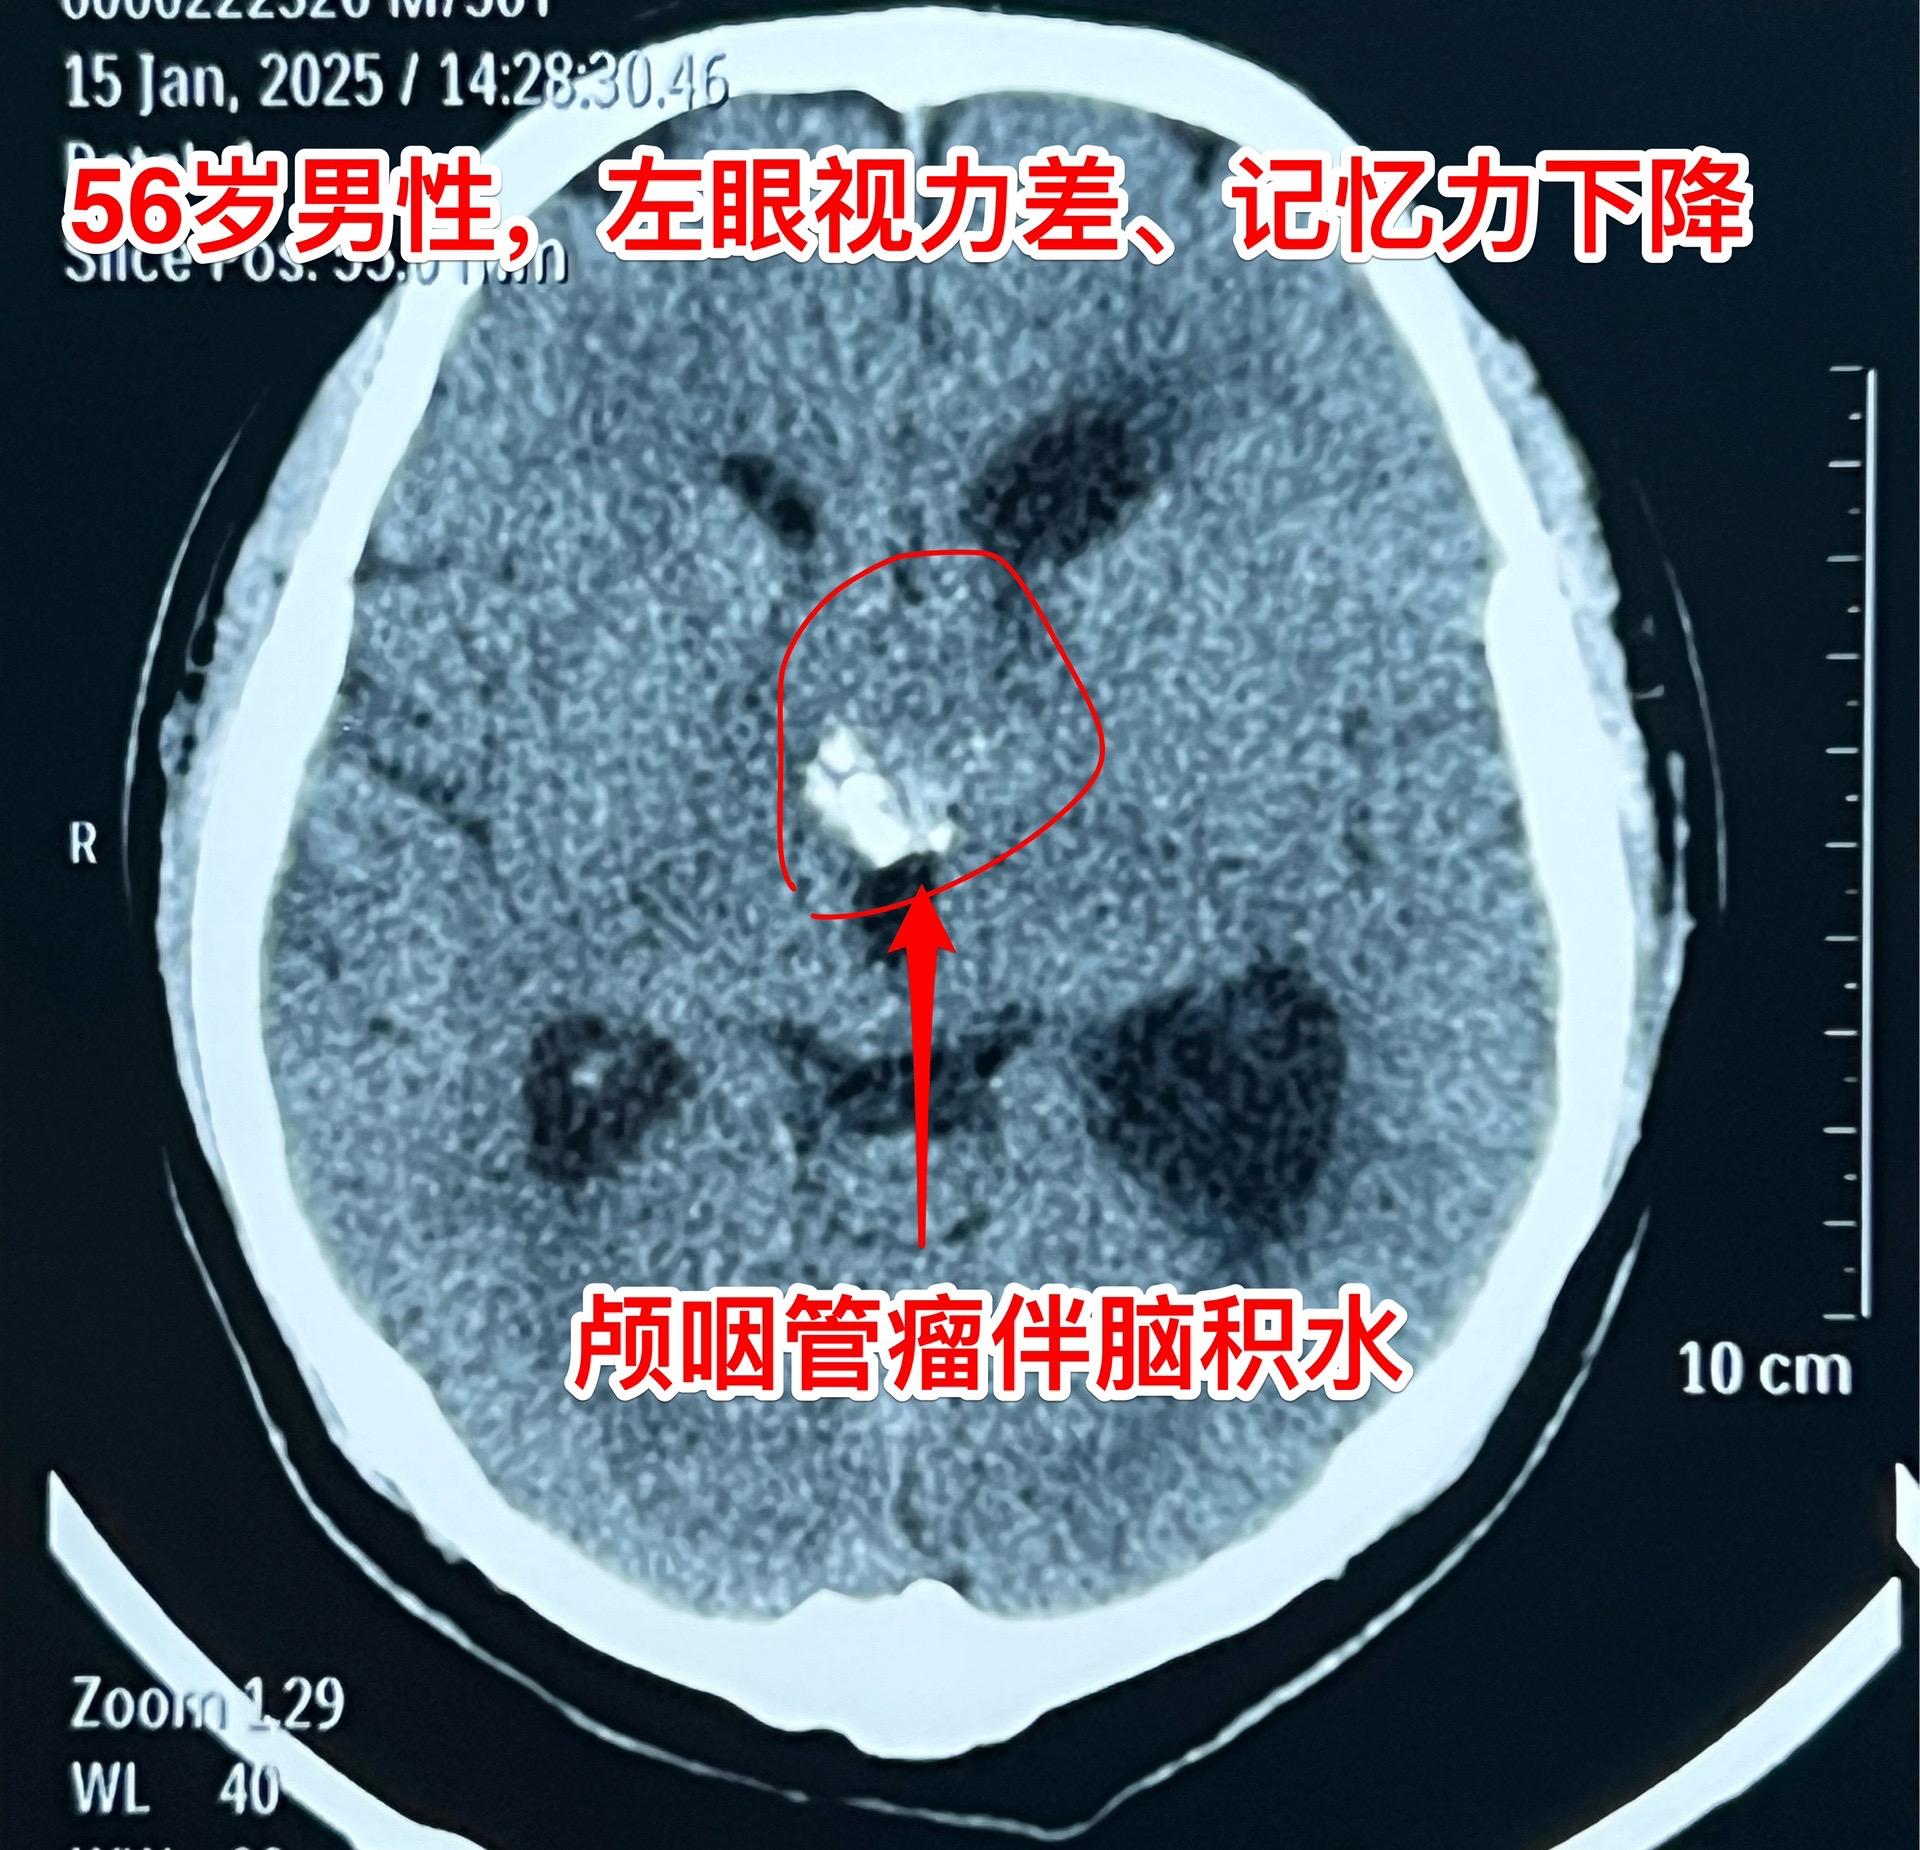

一天两个颅咽管瘤手术,凌晨两点才到家 科里年轻医生说还在关颅。 第一个病人广州人,56岁,左眼视力下降,检查出颅咽管瘤已经半年了,近期出现记忆力下降。病人之前一直在赶在过年前来作手术。今天的手术很顺利。 第二个病人是40岁大同市男性,思维糊涂、精神萎靡,坐轮椅到三博脑科医院就诊,颅咽管瘤伴有脑积水。今天的手术也是很顺利。